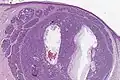

Histologie eines nodulären Basalioms -

Histologie eines sklerodermiformen Basalioms -